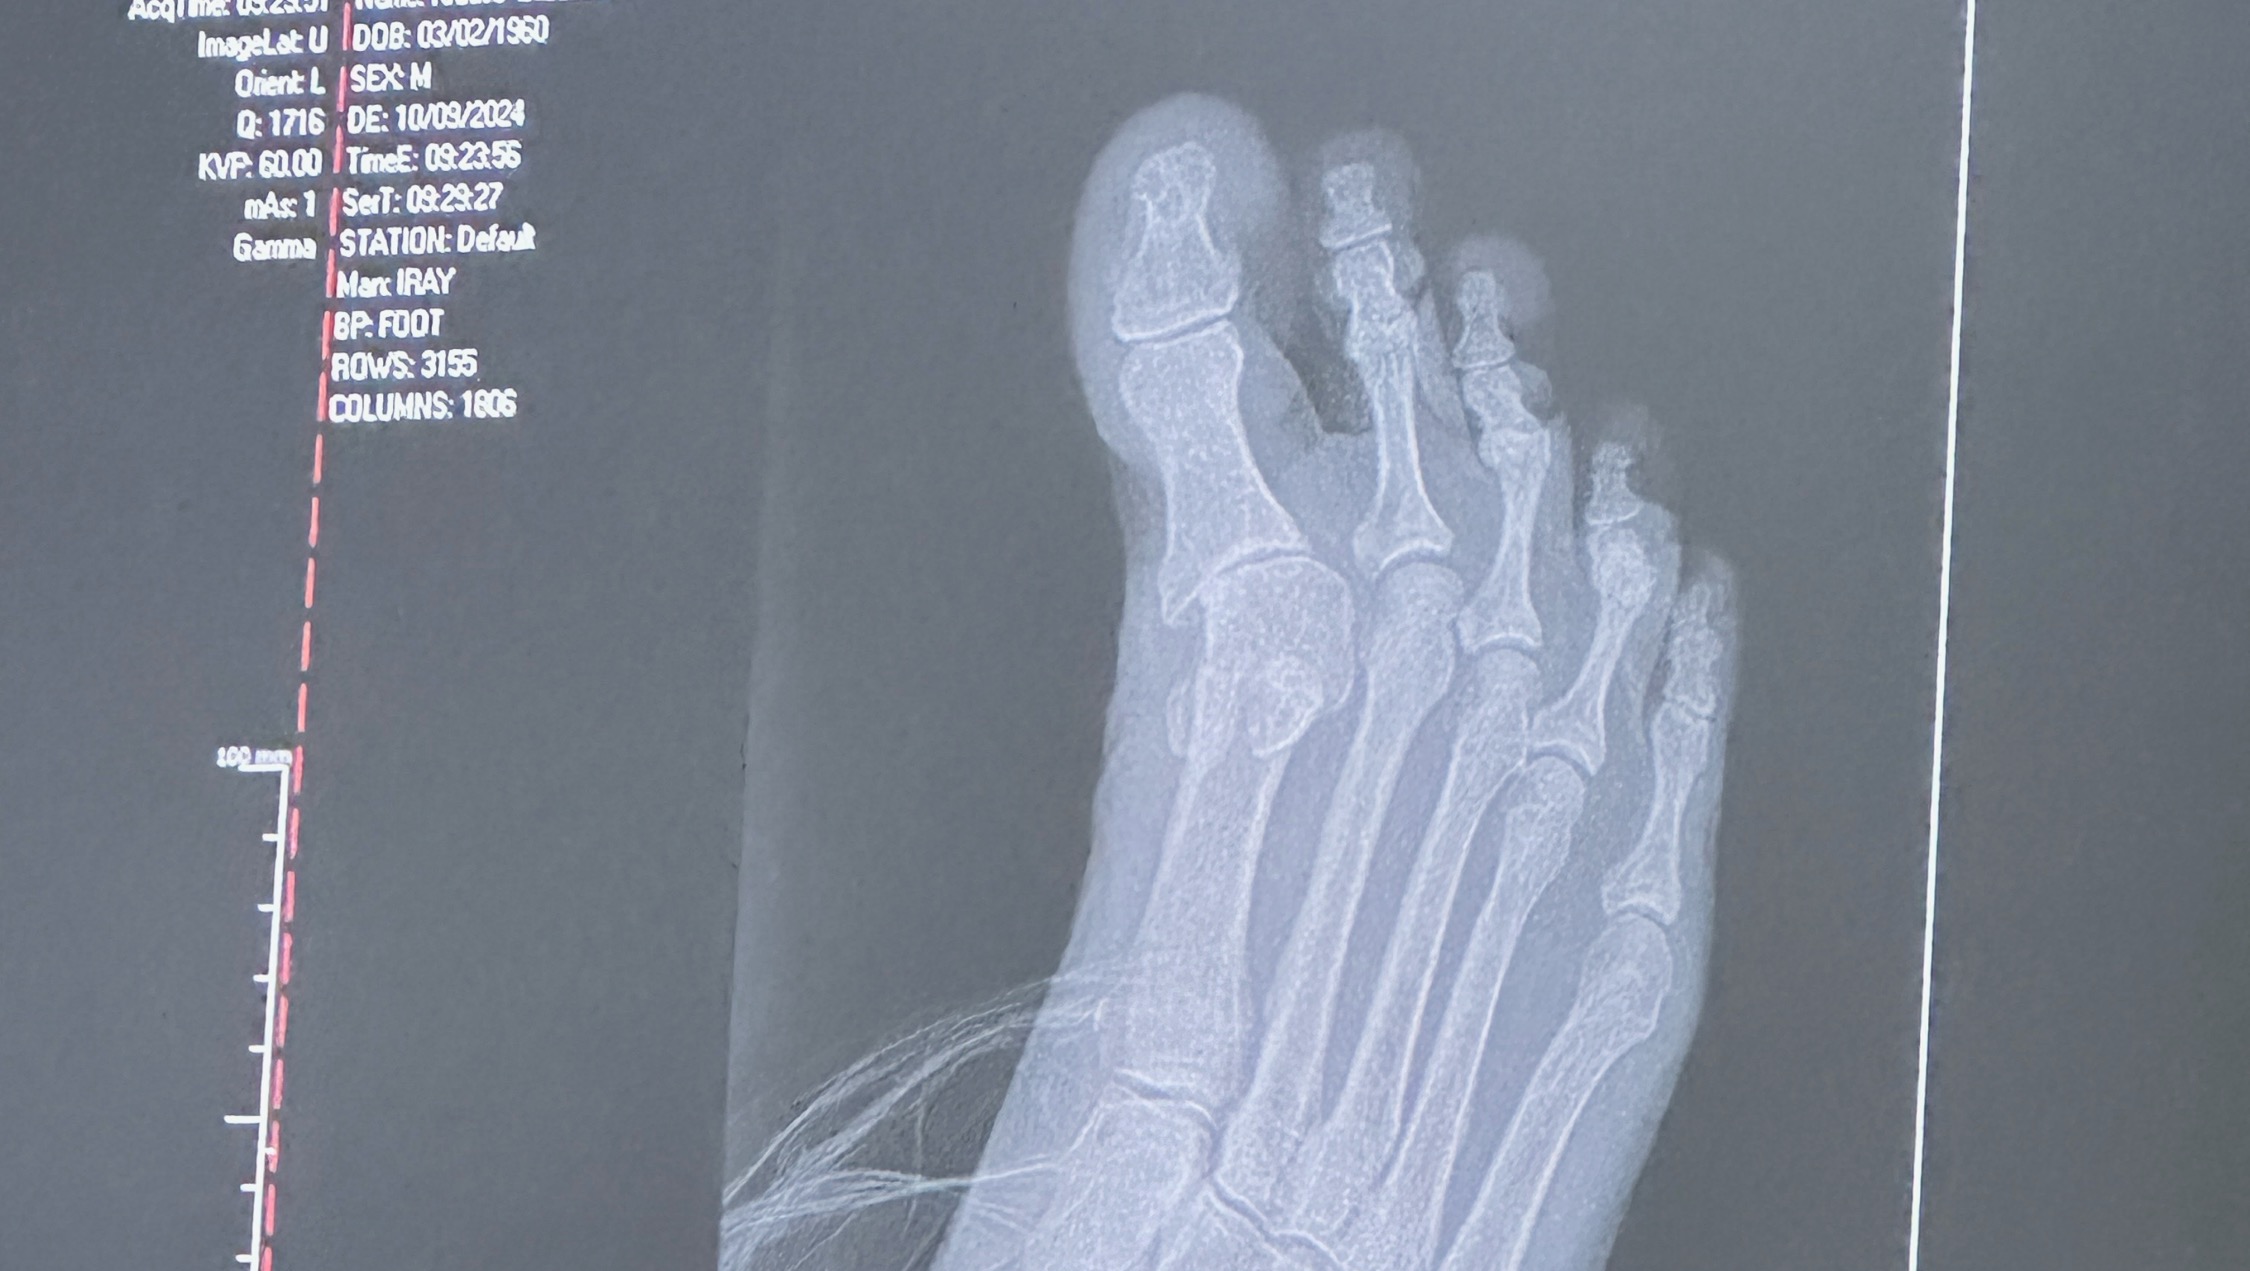

It’s been a hard year here medically. I really need help to get through this next surgery and post operation recovery. due to past nerve damage my right foot has started twisting and has dislocated my big toe joint. This is now affecting my knee ,hip and back. I have surgery scheduled nov 5. I survive on social security disability alone. I need cash for copay before surgery.